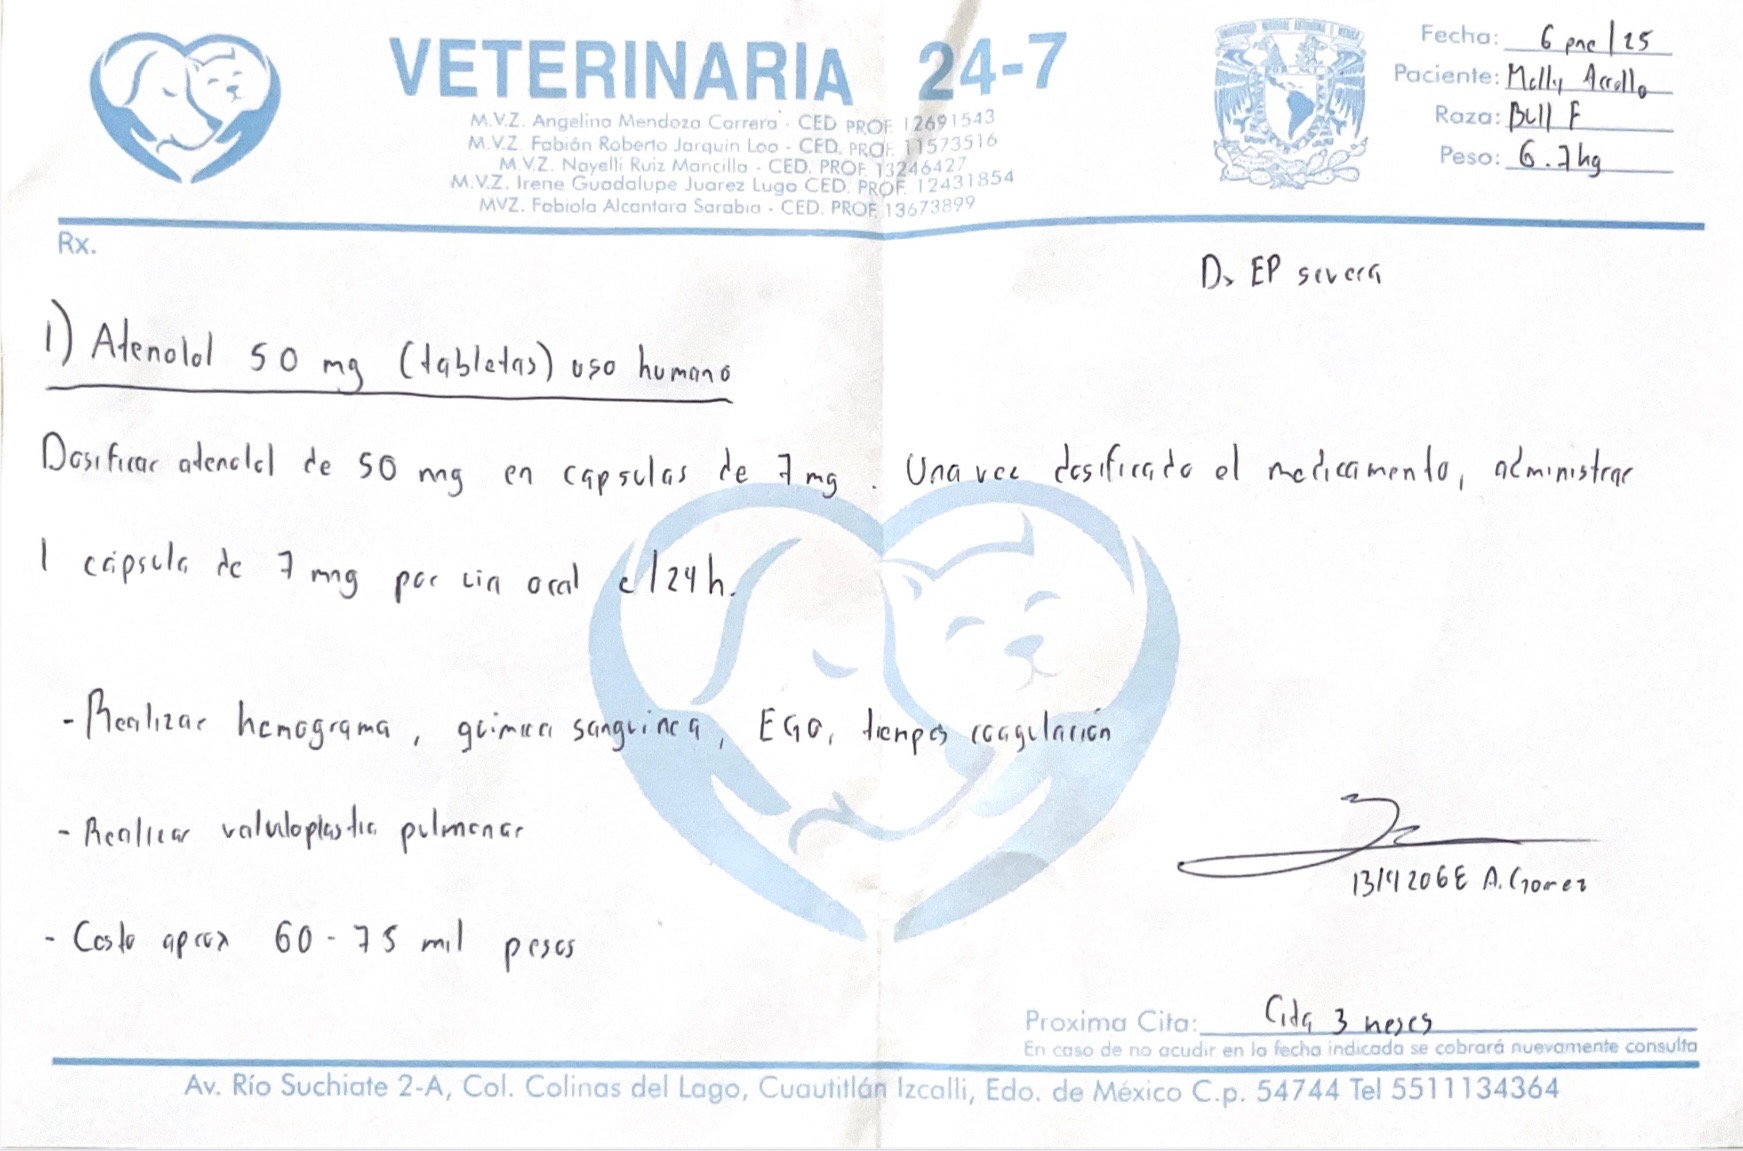

Hola, soy Tamara y estoy recaudando fondos para mi perrita Molly, quien necesita una cirugía de corazón llamada valvuloplastia pulmonar.

Molly tiene casi cinco meses y nació con esta condición congénita (estenosis pulmonar). Fue diagnosticada recientemente mediante electrocardiograma y ecocardiograma, donde confirmaron que su válvula pulmonar no funciona correctamente y su corazón está trabajando con demasiado esfuerzo.

La cirugía cuesta entre $60,000 y $75,000 MXN, y aún necesitamos reunir $40,000 pesos para poder realizarla a tiempo. Molly es una cachorrita llena de vida y queremos darle la oportunidad de crecer sana y seguir a nuestro lado.

Hi, my name is Tamara and I’m raising funds for my puppy Molly, who needs a heart surgery called pulmonary valvuloplasty.

Molly is five months old and was born with this congenital (Pulmonary stenosis). She was recently diagnosed through an electrocardiogram and echocardiogram, which confirmed that her pulmonary valve isn’t working properly and her heart is under severe strain.

The surgery costs between $60,000 and $75,000 MXN, and we still need to raise $40,000 pesos to make it possible. Molly is a loving, playful puppy, and we want to give her the chance to grow healthy and live a full life.